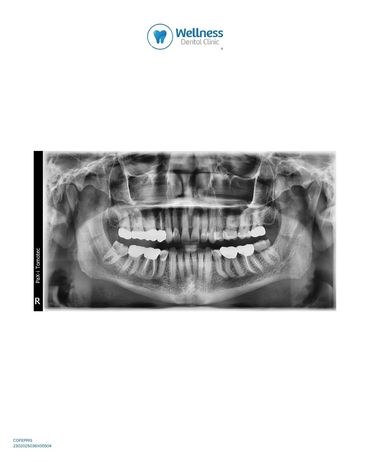

Diagnóstico y tecnología avanzada, todo en un solo lugar

En Wellness Dental Clinic Tijuana, contamos con instalaciones equipadas con tecnología de última generación, donde realizamos tomografías y radiografías dentales sin necesidad de trasladarte a otras locaciones.

Todo al momento, el mismo día.

Comodidad, precisión y rapidez para tu tratamiento.

Diagnostics and advanced technology, all in one place

At Wellness Dental Clinic Tijuana, we have facilities equipped with state-of-the-art technology, where we perform dental CT scans and X-rays without the need to travel to other locations.

📷 All on the spot, on the same day.

Convenience, precision, and speed for your treatment.